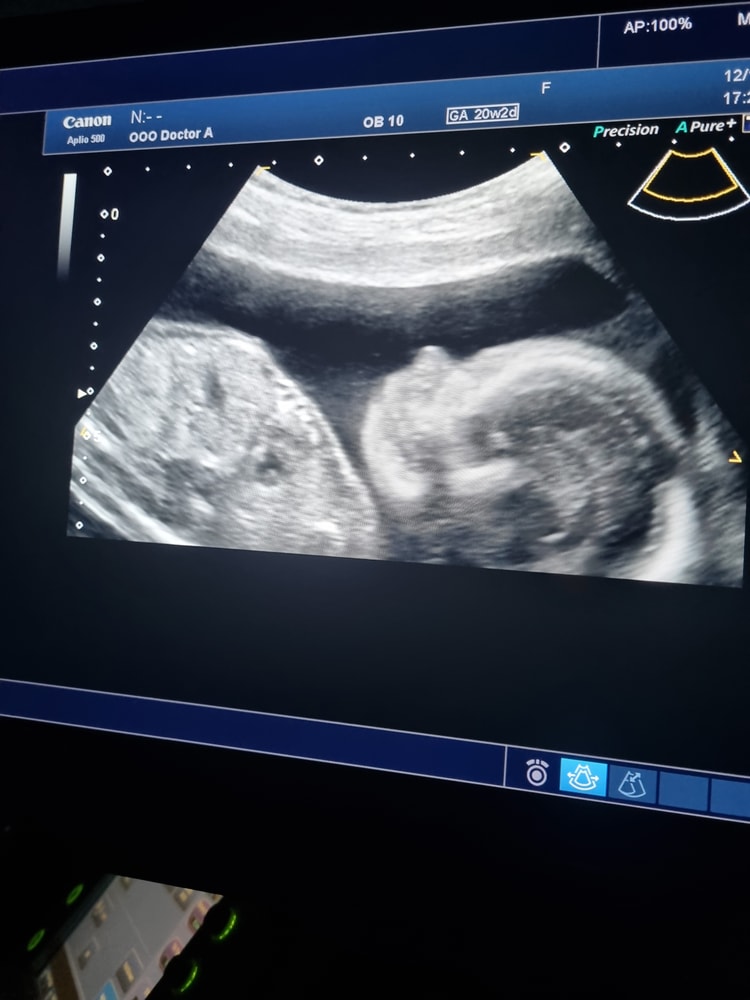

Наша малышка🥰 ходим на узи платно, чтобы хоть взглянуть на неё,а то бесплатно даже на экран посмотреть не дают😅пол узнали также на платном узи. Вес плода предположительно 426 гр. Опережает срок уже дней на 5,какие то параметры на неделю,изначально было на 2-3. Узист говорит, на витамины не налегать))